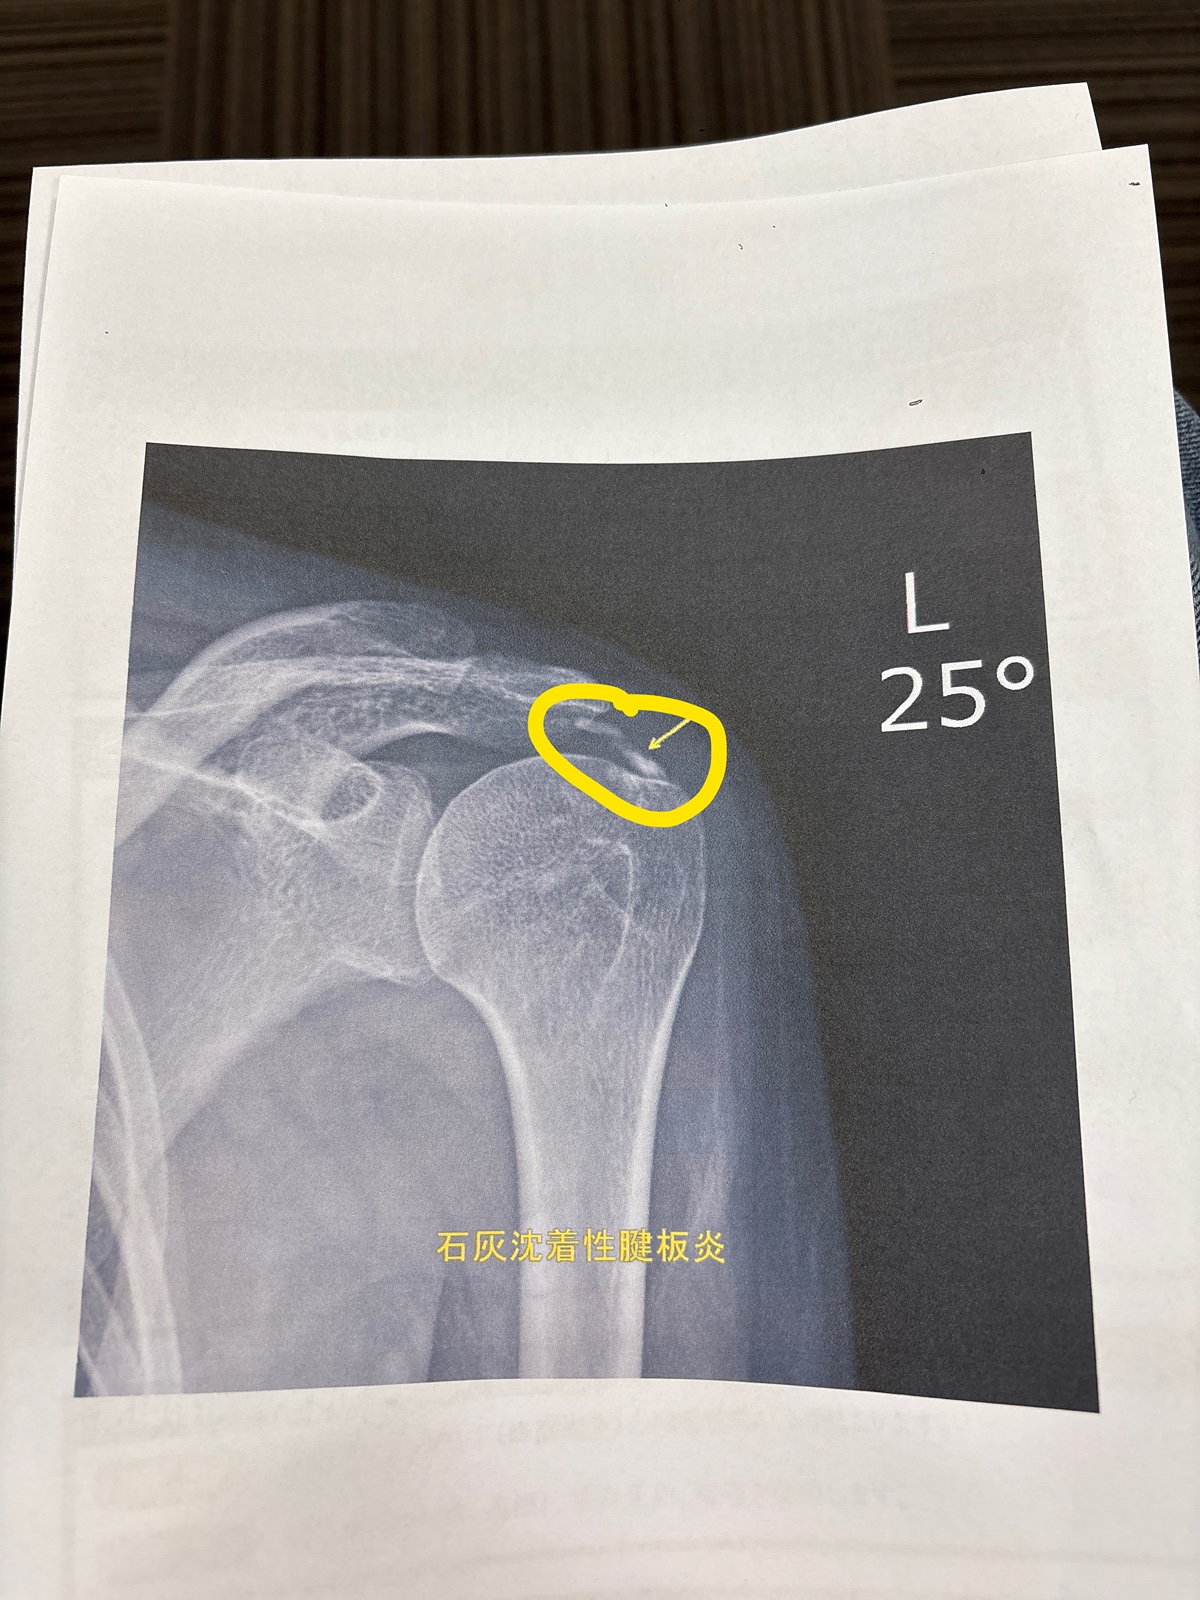

난 어깨에 석회 달고사는데 오늘은 스테로이드 주사 맞고 아파서 움 ㅠ

보통 체외충격파 -> 너무 미치게 아프면 스테로이드 주산데

오늘은 그정도까진 아닌데 주사만 놓고 체외충격파 안해도 된다네ㅠ

아픈지 10년… 하